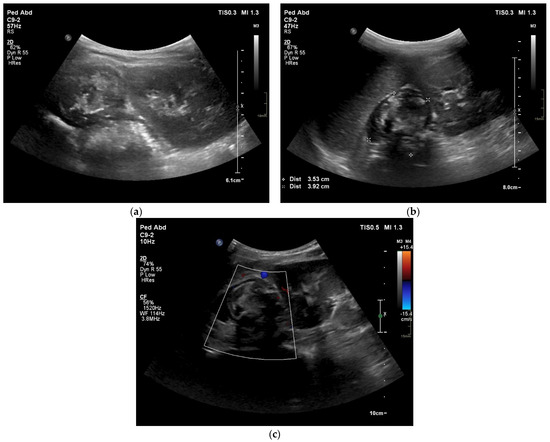

4. Case Presentation

5.3. Imaging